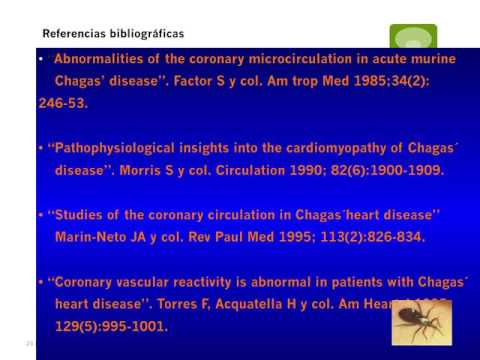

Enfermedad de Chagas 2017: después del BENEFIT. Parte 6/6

Enfermedad de Chagas 2017: después del BENEFIT. Parte 5/6

Enfermedad de Chagas 2017: después del BENEFIT. Parte 4/6

Enfermedad de Chagas 2017: después del BENEFIT. Parte 3/6

Enfermedad de Chagas 2017: después del BENEFIT. Parte 2/6

Enfermedad de Chagas 2017: después del BENEFIT. Parte 1/6